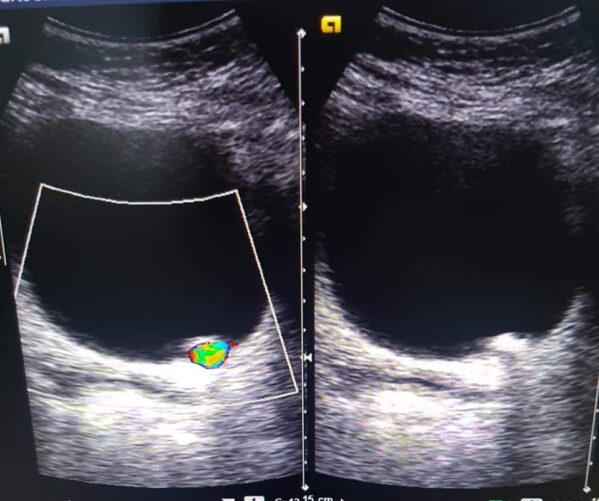

En las imágenes mostramos el caso de un lito (piedra) atorado en la porción más distal del ureter izquierdo cercano a su unión con la vejiga. El diagnóstico se realizó mediante ultrasonido.

Dra. Alejandra Espinoza

Especialista en Radiología.